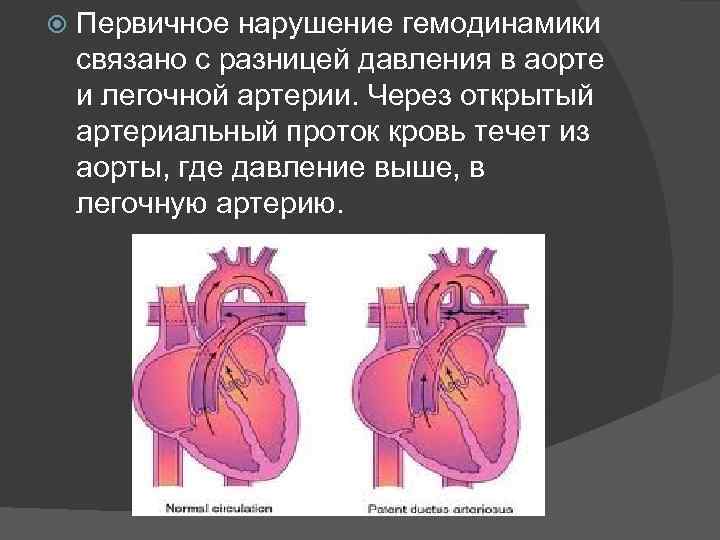

Первичное нарушение гемодинамики связано с разницей давления в аорте и легочной артерии. Через открытый артериальный проток кровь течет из аорты, где давление выше, в легочную артерию.